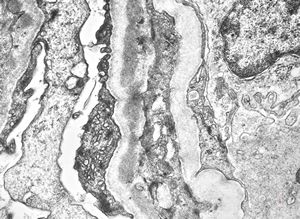

M,17y. | Alport syndrome - split and laminated basement membranes